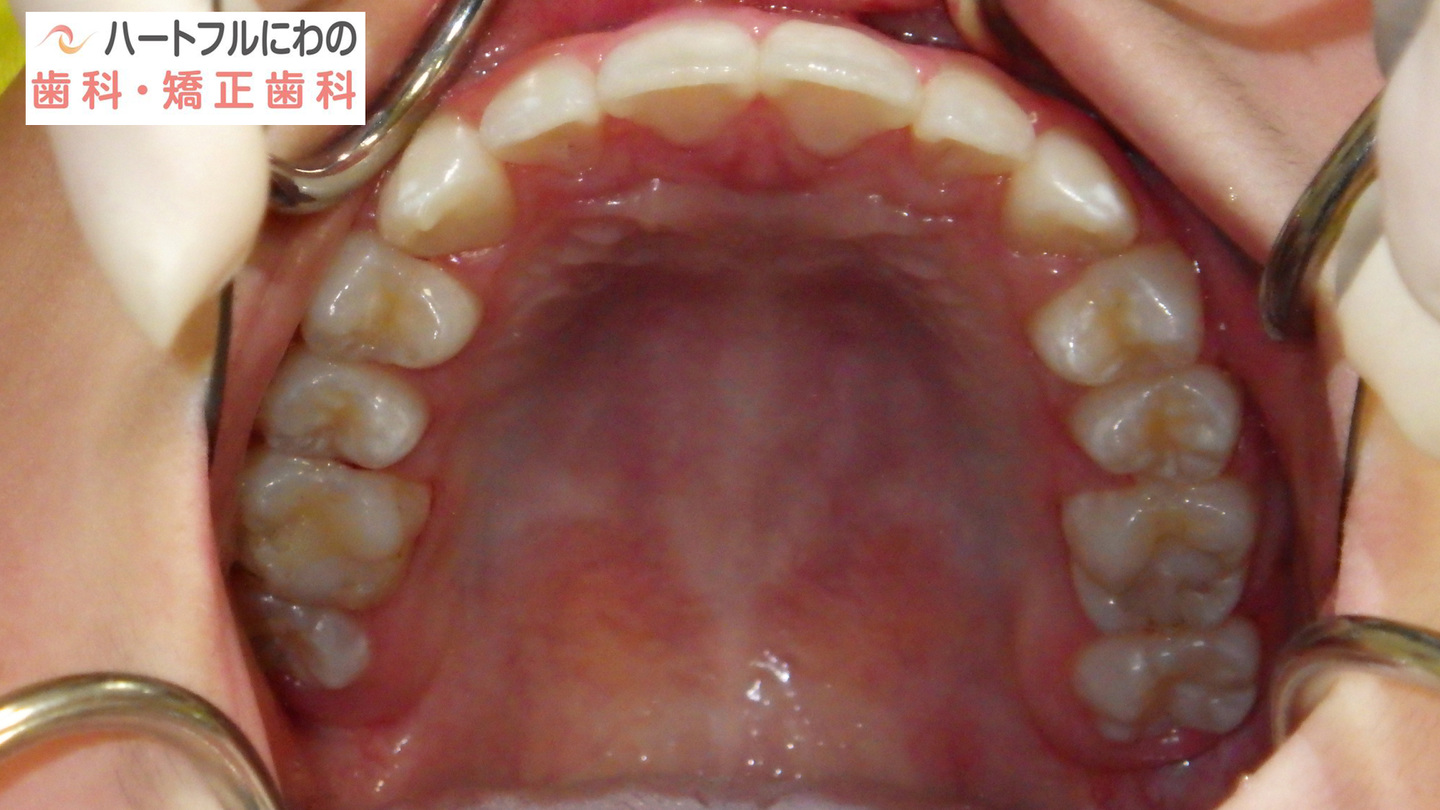

お口の中を拝見すると、上下の叢生(いわゆるガタガタ、乱ぐい)がみられ、多数の虫歯と歯肉炎がみられました。上唇小帯(上唇のすじ)の問題もありました。口呼吸で口腔内が乾燥すると通常の何倍も歯垢が付きやすくなり、虫歯や歯肉炎が頻発します。口呼吸の強い子は重なっている部分のかみ合わせが深い(下の歯がほとんどみえない)のもよく見られる特徴です。

奥歯と前歯の前後的位置関係は大きく改善し、正常になりました。